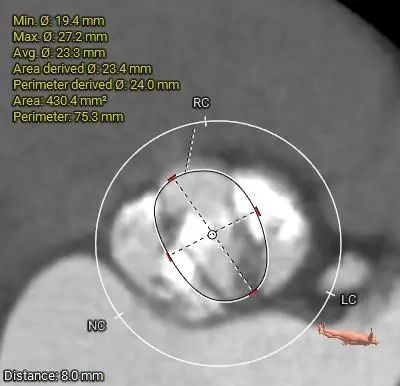

ANNULUS

8mm SUPRA ANNULUS